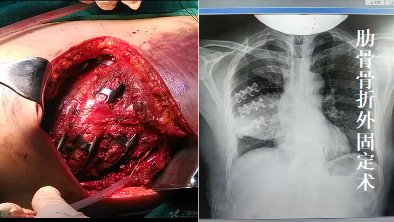

对于肺部良、恶性肿瘤(肺结节或肺大疱等)能行胸腔镜下肺叶乃至肺段切除术,具有创伤小、恢复快、治疗彻底的特点。对胸部食管、食管胃结合处的良恶性肿瘤诊疗经验丰富,治疗规范。对纵膈各类肿瘤亦能做到微创切除,副损伤小等